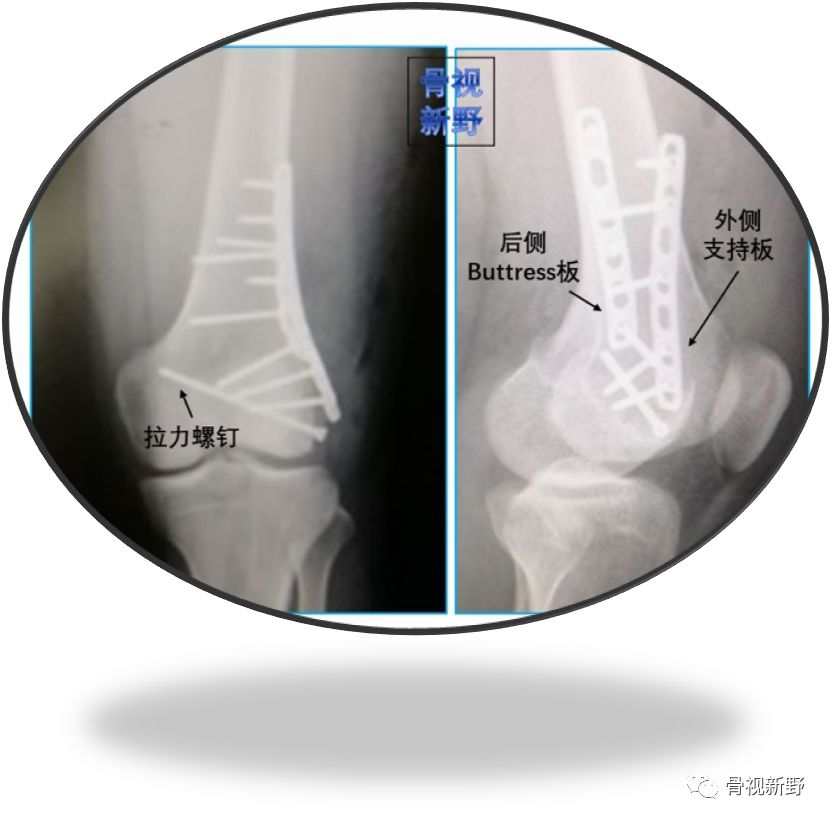

小直径拉力螺钉+侧方支持钢板+后方Buttress重建钢板

小直径拉力螺钉+LCP侧方支持钢板+后方Buttress钢板